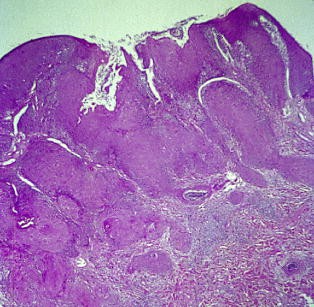

Das klinische Bild der PVL entsprach den in der Literatur beschriebenen Kriterien. Die mittlere Beobachtungsdauer war mit 1,7 Jahren kurz. 3,6 unterschiedliche Lokalisationen von PVL pro Patientin waren zu beobachten. Die Wangenschleimhaut, der zahnlose Alveolarfortsatz und die Gingiva propria waren am häufigsten betroffen. Eine Patientin hatte bereits zum Zeitpunkt der Überweisung ein Karzinom entwickelt. Bei den übrigen Frauen traten im Beobachtungszeitraum Karzinome auf. Unterschiedliche Therapien konnten Rezidive bzw. das Neuauftreten von Zweitkarzinomen nicht verhindern. 2 Patientinnen verstarben an PVL. Histopathologisch ergab sich ein für PVL typisches Spektrum. Homogene plane Leukoplakien zeigen Akanthose, Hyperkeratose und häufig Parakeratose ohne Zeichen einer Epitheldysplasie. Das proliferative verruköse Stadium ist gekennzeichnet durch papillomatöse Epithelveränderungen mit Zeichen geringer Dysplasie des Epithels und subepithelialer Infiltration mit immunkompetenten Zellen. Transformationen führen zu verrukösen Karzinomen oder Plattenepithelkarzinomen.

The clinical appearance of PVL was characteristic as compared to criteria described in the literature. The average period of observation in these cases was short (1.7 years). There were 3.6 different localizations observed per patient. The buccal mucosa, gingiva, and edentulous alveolar ridge were most often affected. One patient had already developed squamous cell carcinoma prior to referral. The others developed malignancies during follow-up. Recurrences and secondary malignancies could not be avoided using different therapeutic modalities. Two patients died from PVL. The characteristic spectrum of histopathological findings in PVL was observed. Homogenous flat leukoplakias are characterized by acanthosis, hyperkeratosis, and often parakeratosis. Epithelial dysplasia is not seen. The proliferative verrucous stage of the disease is characterized by papillomatous epithelial growths with signs of slight epithelial dysplasia and subepithelial infiltration with immunocompetent cells. Stages of transformation may result in verrucous carcinoma or squamous cell carcinoma.